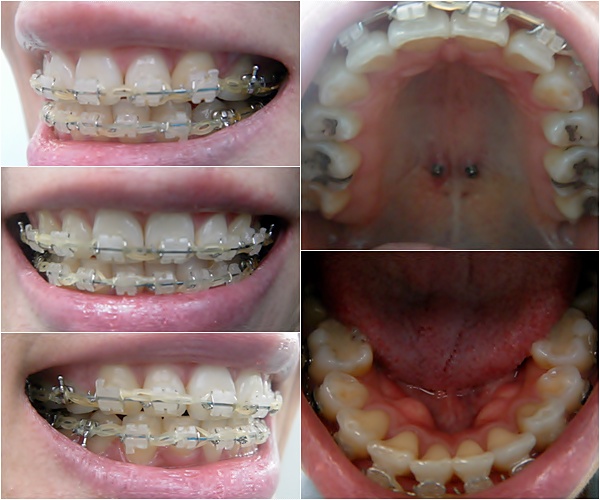

오라픽스 3D 개인맞춤 치아교정장치 붙이고 나서 월치료~

정말 하나도 안 아프게 살살 조심스럽게~ 와이어 교체해주시고~ 파워체인 연결해주셨어요~ ㅎㅎ

오라픽스장치 월치료는 일반장치 월치료랑 비슷하게~

와이어 바꾸고 파워체인 새로 연결하는 걸로~ 진료 끄읕~ ^**^

그리고 27번째 월치료는요~ ' ㅁ')//

라인이 살짝 안 맞는 아래 앞니를 맞추기 위해 와이어를 구부리고 파워체인을 한바퀴 감아 당겨 주었어요~

두꺼운 와이어로 교체하고 파워체인 연결하고~

진료 끝나고 나서 다시 고무줄 걸기~

작은 고무줄을 이용해서 요렇게 삼각형 모양으로 거니까~